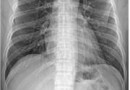

늑골골절

갈비뼈(rib,늑골)는 아래와 같이 12개가 양쪽으로 있으며, 뒤쪽 흉추(thoracic spine)부터 앞쪽 흉골(sternum)과 연골에 붙어있습니다. 원인​​ 대부분는 부딪히거나, 직접적으로 맞아서 골절이 생기게 되며, 드물게 기침을 심하게 하거나, 골…